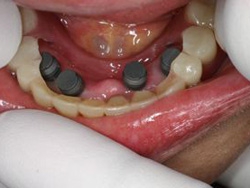

術前術前主訴-総入れ歯の安定が悪い 即時加重可能のミニインプラント使用した。 術前レントゲン術前レントゲン術前レントゲン CT撮影から3次元骨モデルを作成CT撮影から3次元骨モデルを作成CT撮影から3次元骨モデルを作成し埋入位置の確認 フィクスチャーを浸潤麻酔下で埋入フィクスチャーを浸潤麻酔下で埋入。歯茎を切らないので患者さんも非常に楽

4本埋入終了4本埋入終了4本埋入終了(このシステムは4本が絶対条件) 義歯の調整義歯の調整当日に義歯の調整に取りかかる。裏側より義歯をくりぬき維持部のカバー(ハウジング)を義歯の内面に埋め込む step1 義歯の調整義歯の調整当日に義歯の調整に取りかかる。裏側より義歯をくりぬき維持部のカバー(ハウジング)を義歯の内面に埋め込む step2 義歯の調整当日に義歯の調整に取りかかる。裏側より義歯をくりぬき維持部のカバー(ハウジング)を義歯の内面に埋め込む step3

義歯の調整義歯の調整当日に義歯の調整に取りかかる。裏側より義歯をくりぬき維持部のカバー(ハウジング)を義歯の内面に埋め込む step4 義歯の調整義歯の調整当日に義歯の調整に取りかかる。裏側より義歯をくりぬき維持部のカバー(ハウジング)を義歯の内面に埋め込む step5 義歯の裏側義歯の裏側義歯の裏側 装着後しっかり噛める様になる